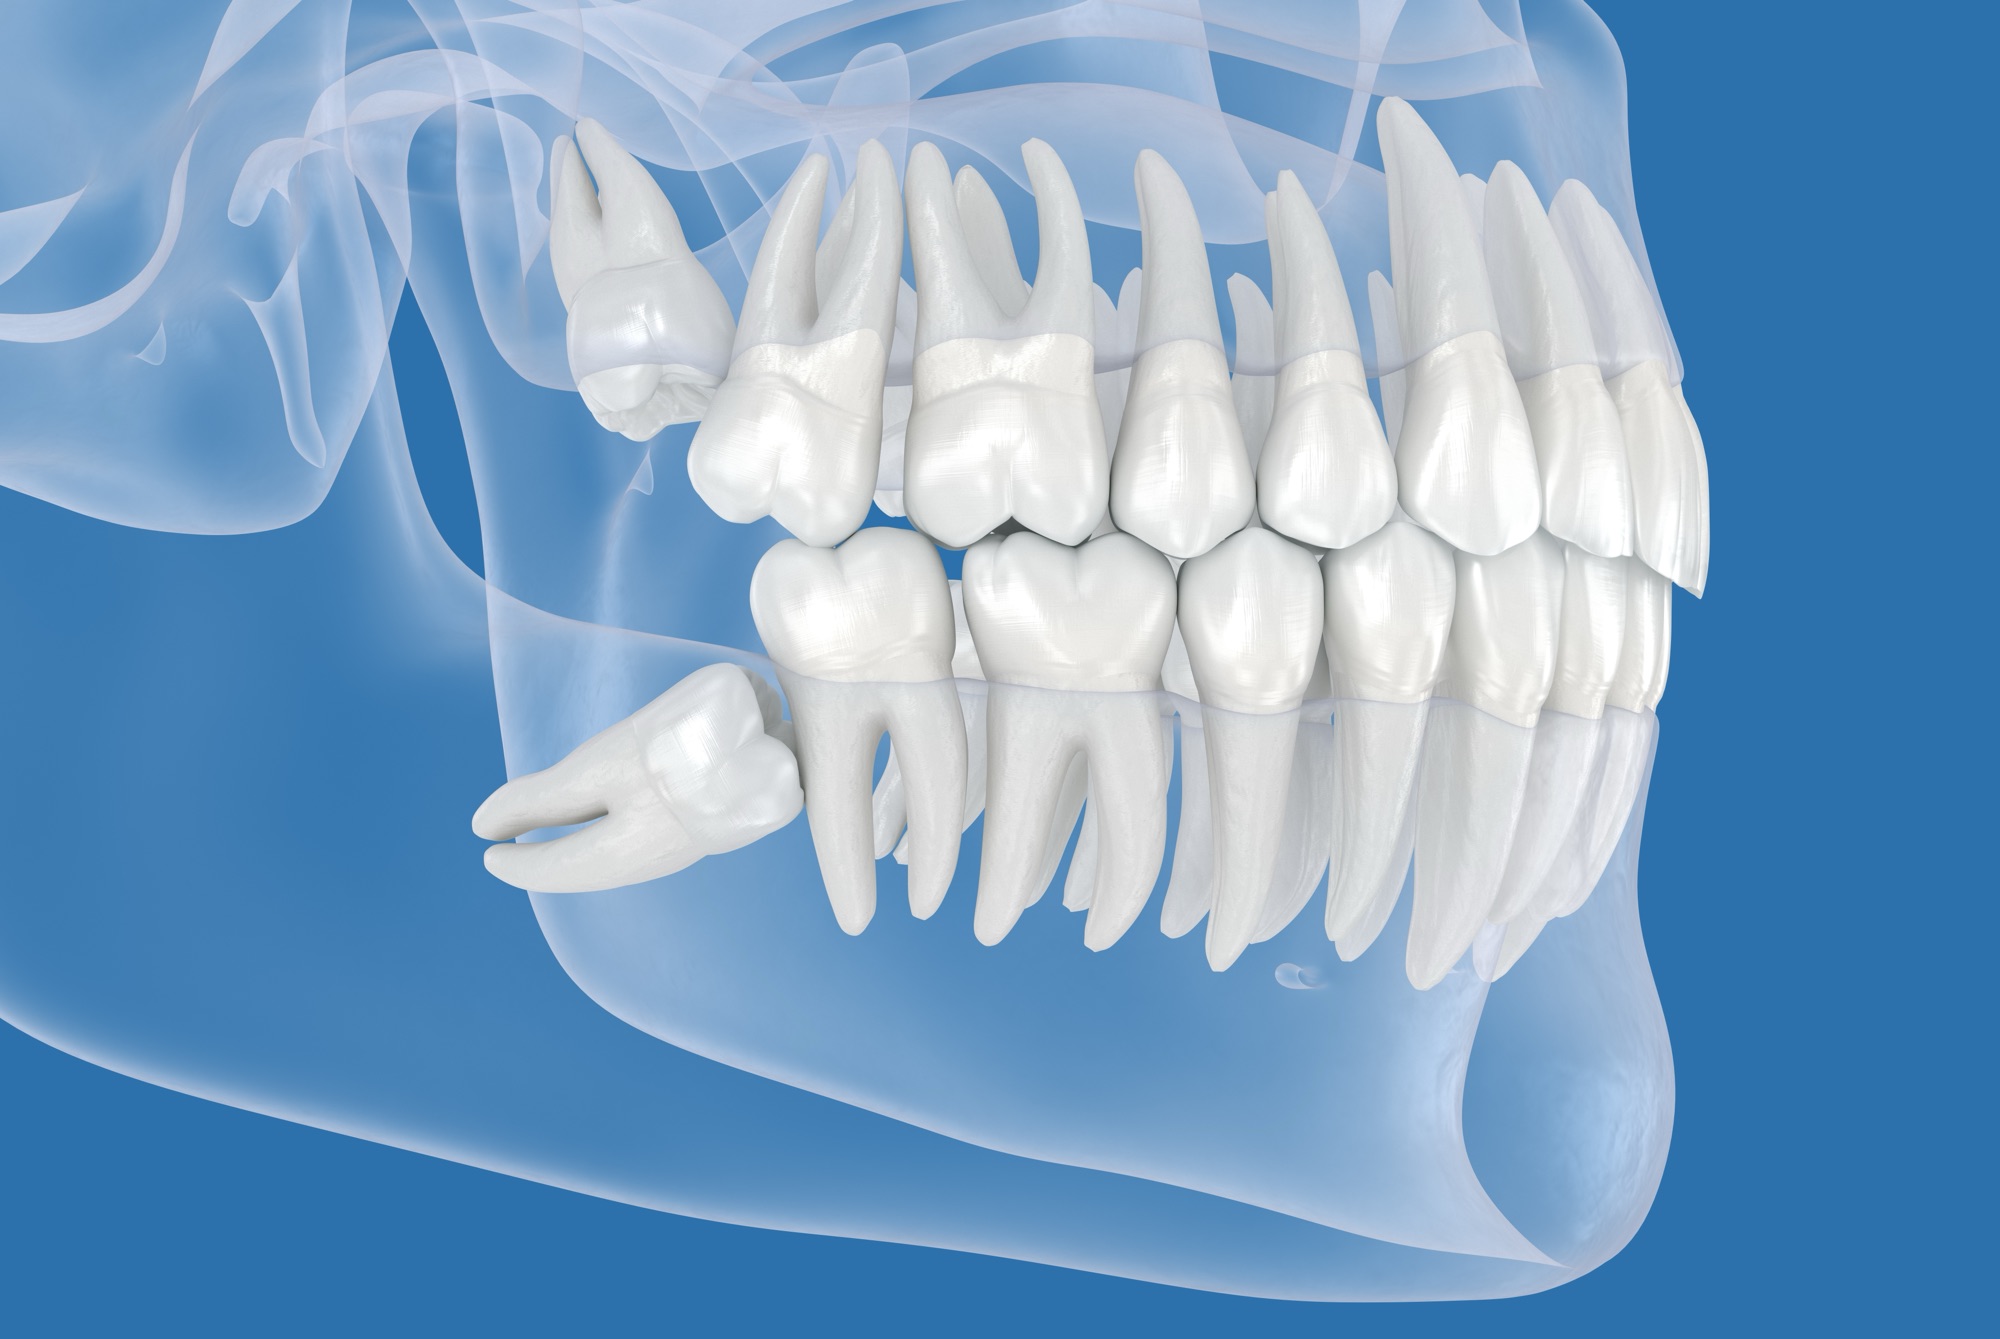

歯科用CTによる精密なシミュレーション

横向きに生えた歯(水平埋伏智歯)の抜歯で最も重要なのは、事前の診断です。最新の歯科用CTを用い、指導医が神経や血管の位置を3次元的に解析。ミリ単位の精度で安全な手術ルートを決定します。